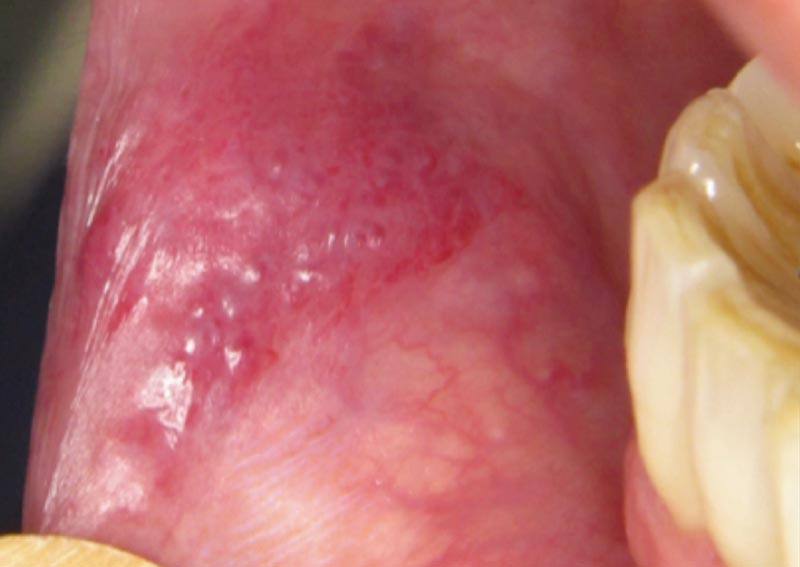

CAS 2

Motif de la consultation. Patiente de 33 ans qui a consulté après la découverte d’une plaque rouge sur la lèvre inférieure droite.

Histoire de la maladie. La patiente se plaignait d’une gêne labiale inférieure apparue 6 mois avant la consultation.